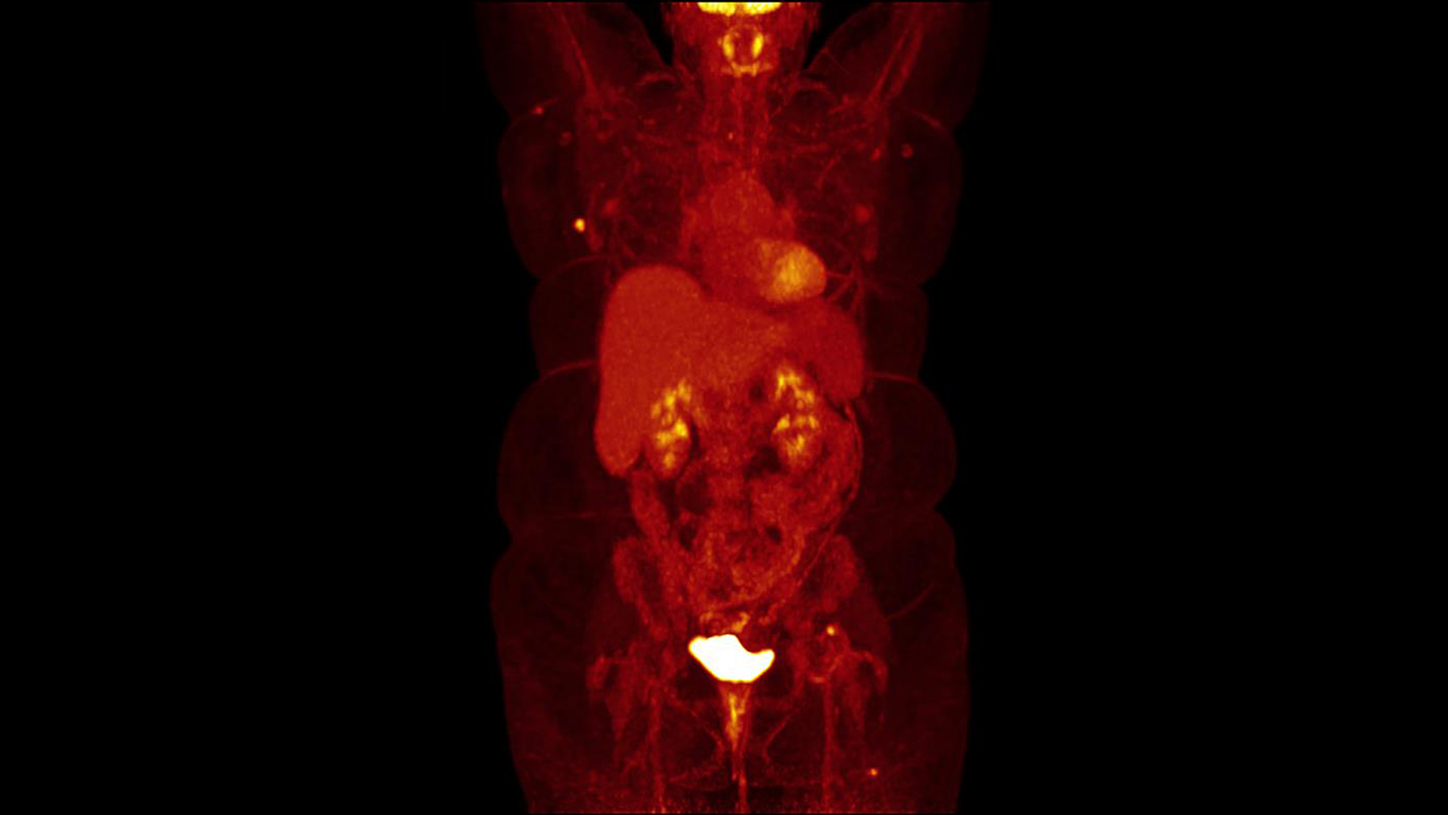

Answering to clinical needs in oncology, neurology, cardiology, and radiology, Siemens Healthineers Molecular Imaging systems provide PET/CT, SPECT, and hybrid SPECT scanner (SPECT/CT) solutions to help clinicians diagnose, treat, and monitor diseases more confidently.